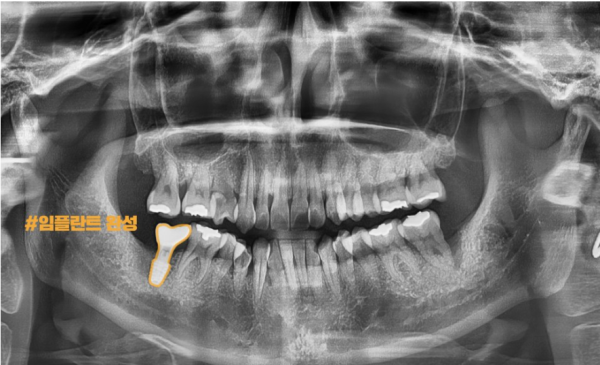

이 환자분께서는 오른쪽 치아 통증을 호소하셨는데요.

파노라마 엑스레이 사진을 보면 양쪽 어금니쪽에 모두 염증이 생겨 잇몸뼈가

녹아버린 상태로 보입니다. 이렇게 양쪽이 모두 상태가 안좋으면 더 문제가 큰 쪽부터

치료를 해야 하기 때문에 오른쪽 어금니부터 임플란트를 하기로 하였습니다.

This patient complained of right tooth pain.

If you look at the panoramic X-ray, both molars are inflamed, and the gum bones are

It looks like it's melted. If both sides are not in good condition, the bigger problem will start

Since I need to treat it, I decided to start with my right molar.